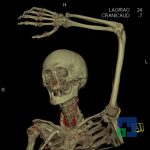

În cazul traumatismelor cranio-cerebrale:

- Diagnosticul fracturilor:

- Unice

- Multiple

- Cu înfundare

- Complexe cranio-sinusale

- Complexe cranio-etmoidale

- Complexe cranio-orbitare

- Complexe cranio-faciale